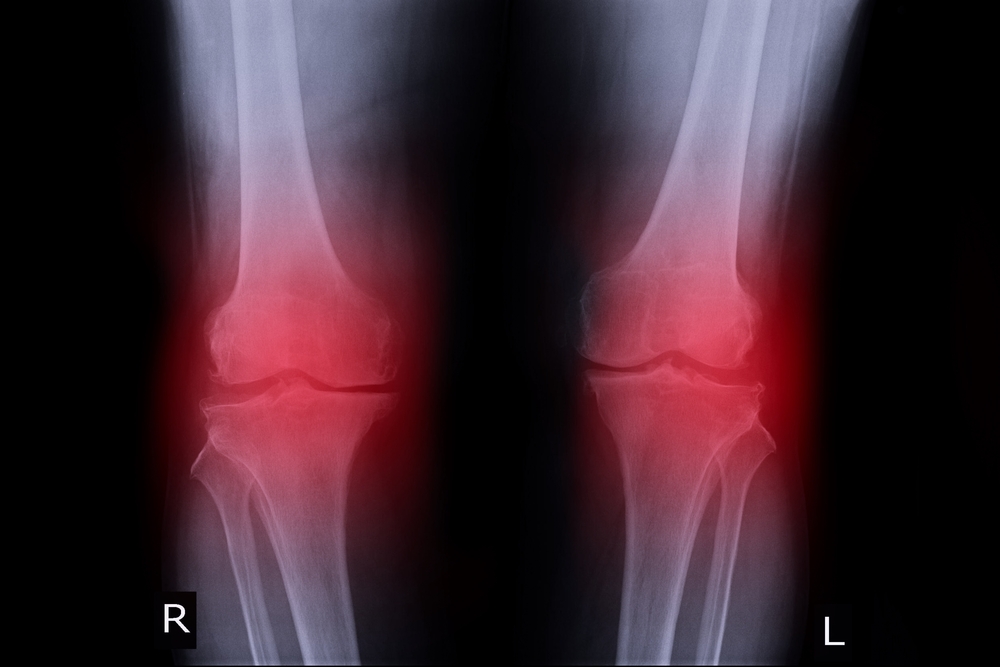

3. Arthritis

- Osteoarthritis – The most common form of arthritis, osteoarthritis is a wear-and-tear condition that occurs when the cartilage in your knee deteriorates with use and age.

- Rheumatoid Arthritis – An autoimmune condition that can affect any joint in your body, including the knees. It causes painful swelling and can eventually result in joint deformity and bone erosion.